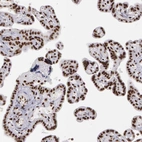

Immunohistochemical staining of human small intestine shows strong nuclear positivity in glandular cells.